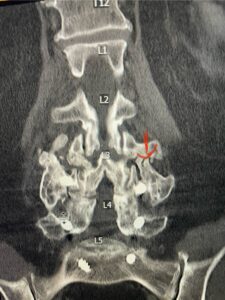

Fig 1b: axial T2-weighted MRI demonstrating severe lumbar stenosis (red arrow)

In patients who have lumbar spinal stenosis and significant cardio/pulmonary conditions, surgery is the last resort. However, some patients with these conditions may fail all means of conservative management where surgery becomes their only option for relief. In those patients, one should strive to do the least complex surgery that is necessary to get the job done for them. In this case study, we are confronted with a new problem in a 78 year-old male patient that was in poor medical condition who had had two prior lumbar laminectomies with resultant fusion and instrumentation from L4-S1. There was now retrolisthesis of L2-3 with severe stenosis (Fig.1)